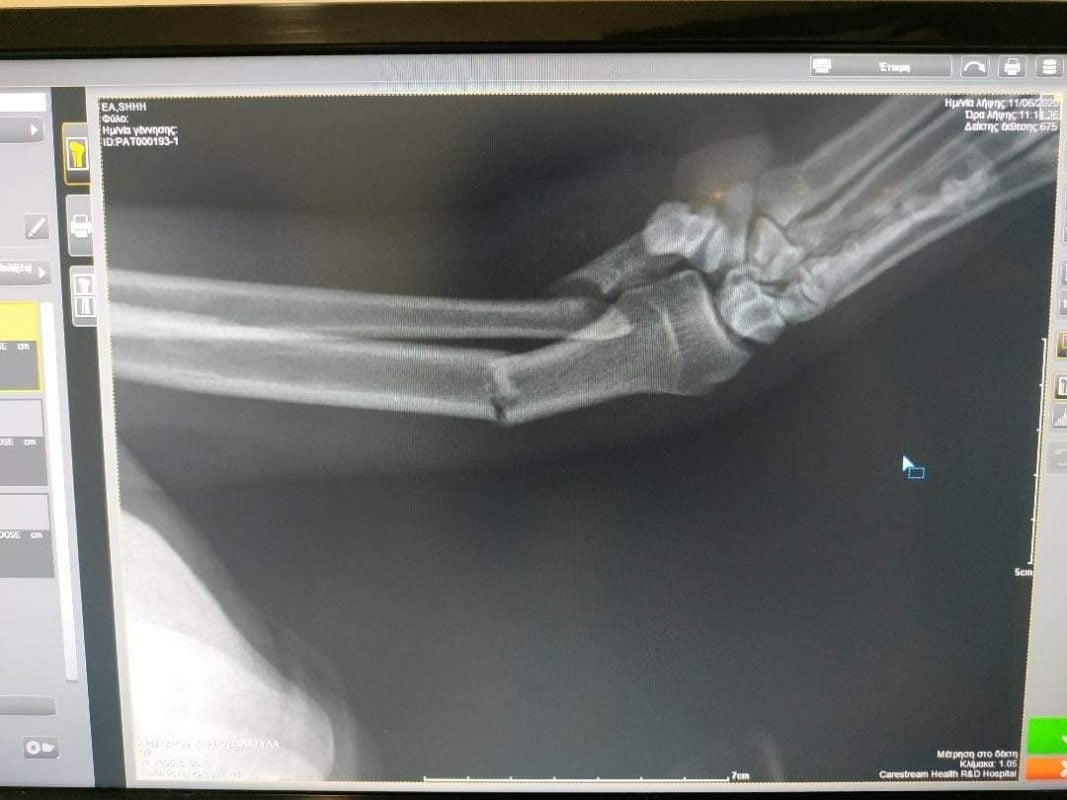

Πριν λίγες μέρες ήταν άτυχος, τον χτύπησε αυτοκίνητο. Δυσκολευτήκαμε να τον μαζέψουμε, αλλά τελικά τα καταφέραμε. Τον πήγαμε στον κτηνίατρο και δυστυχώς οι υποψίες μας βγήκαν αληθινές: έχει κάταγμα και μάλιστα διπλό.

Απαραίτητη είναι η επέμβαση ορθοπεδικού κτηνιάτρου.

veterinarian and unfortunately our suspicions came true: he has a fracture and even a double. Surgery is necessary